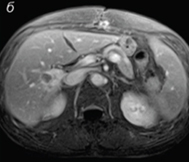

Ядрено-магнитен резонанс преди лечението

ЯМР след 30-дневен курс